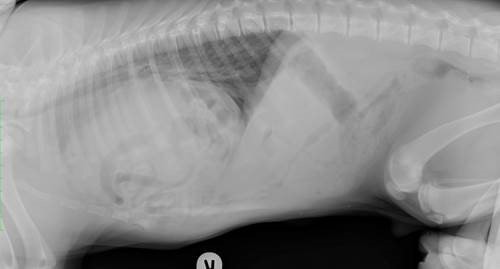

The owners of a black Labrador thought there was something fishy going on when he began vomiting, yelping in pain and acting out of character.